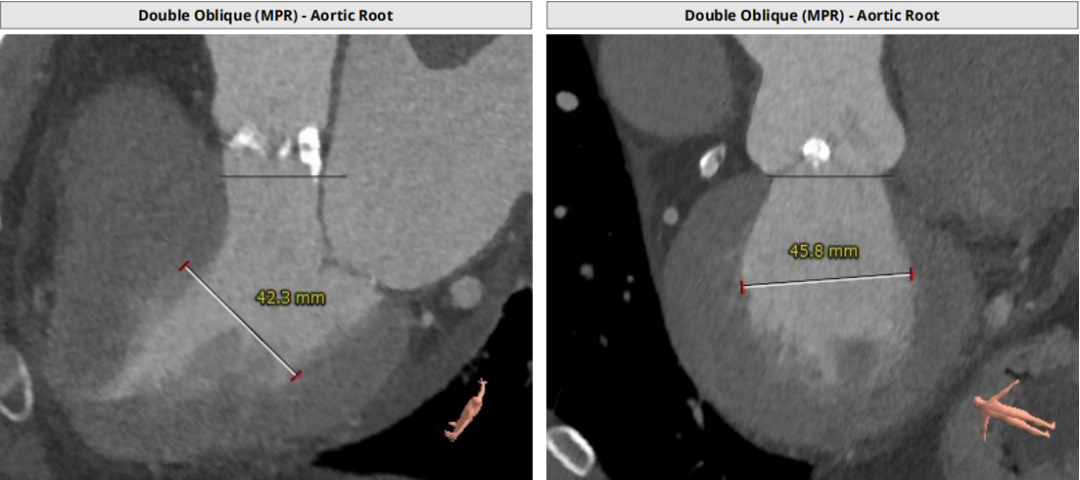

术前CT评估:

瓣环平均直径:25.2mm,左室流出道平均直径:25.5mm;

升主动脉(未见)明显扩张,心脏角度:47°;

左冠高度:12.1mm,右冠高度:16.1mm。

Annulus:25.2mm

LVOT:25.5mm

Sinus:22.1mm*32.6mm STJ:30.3mm

升主:34mm*34.7mm 主动脉成角:47°

钙化积分:272